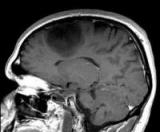

Вы можете контролировать аллергические реакции кожи. Вернее, это способен делать ваш мозг.

Команда нейробиологов обнаружила, что если человек абстрагируется от собственного тела, то иммунная система также...